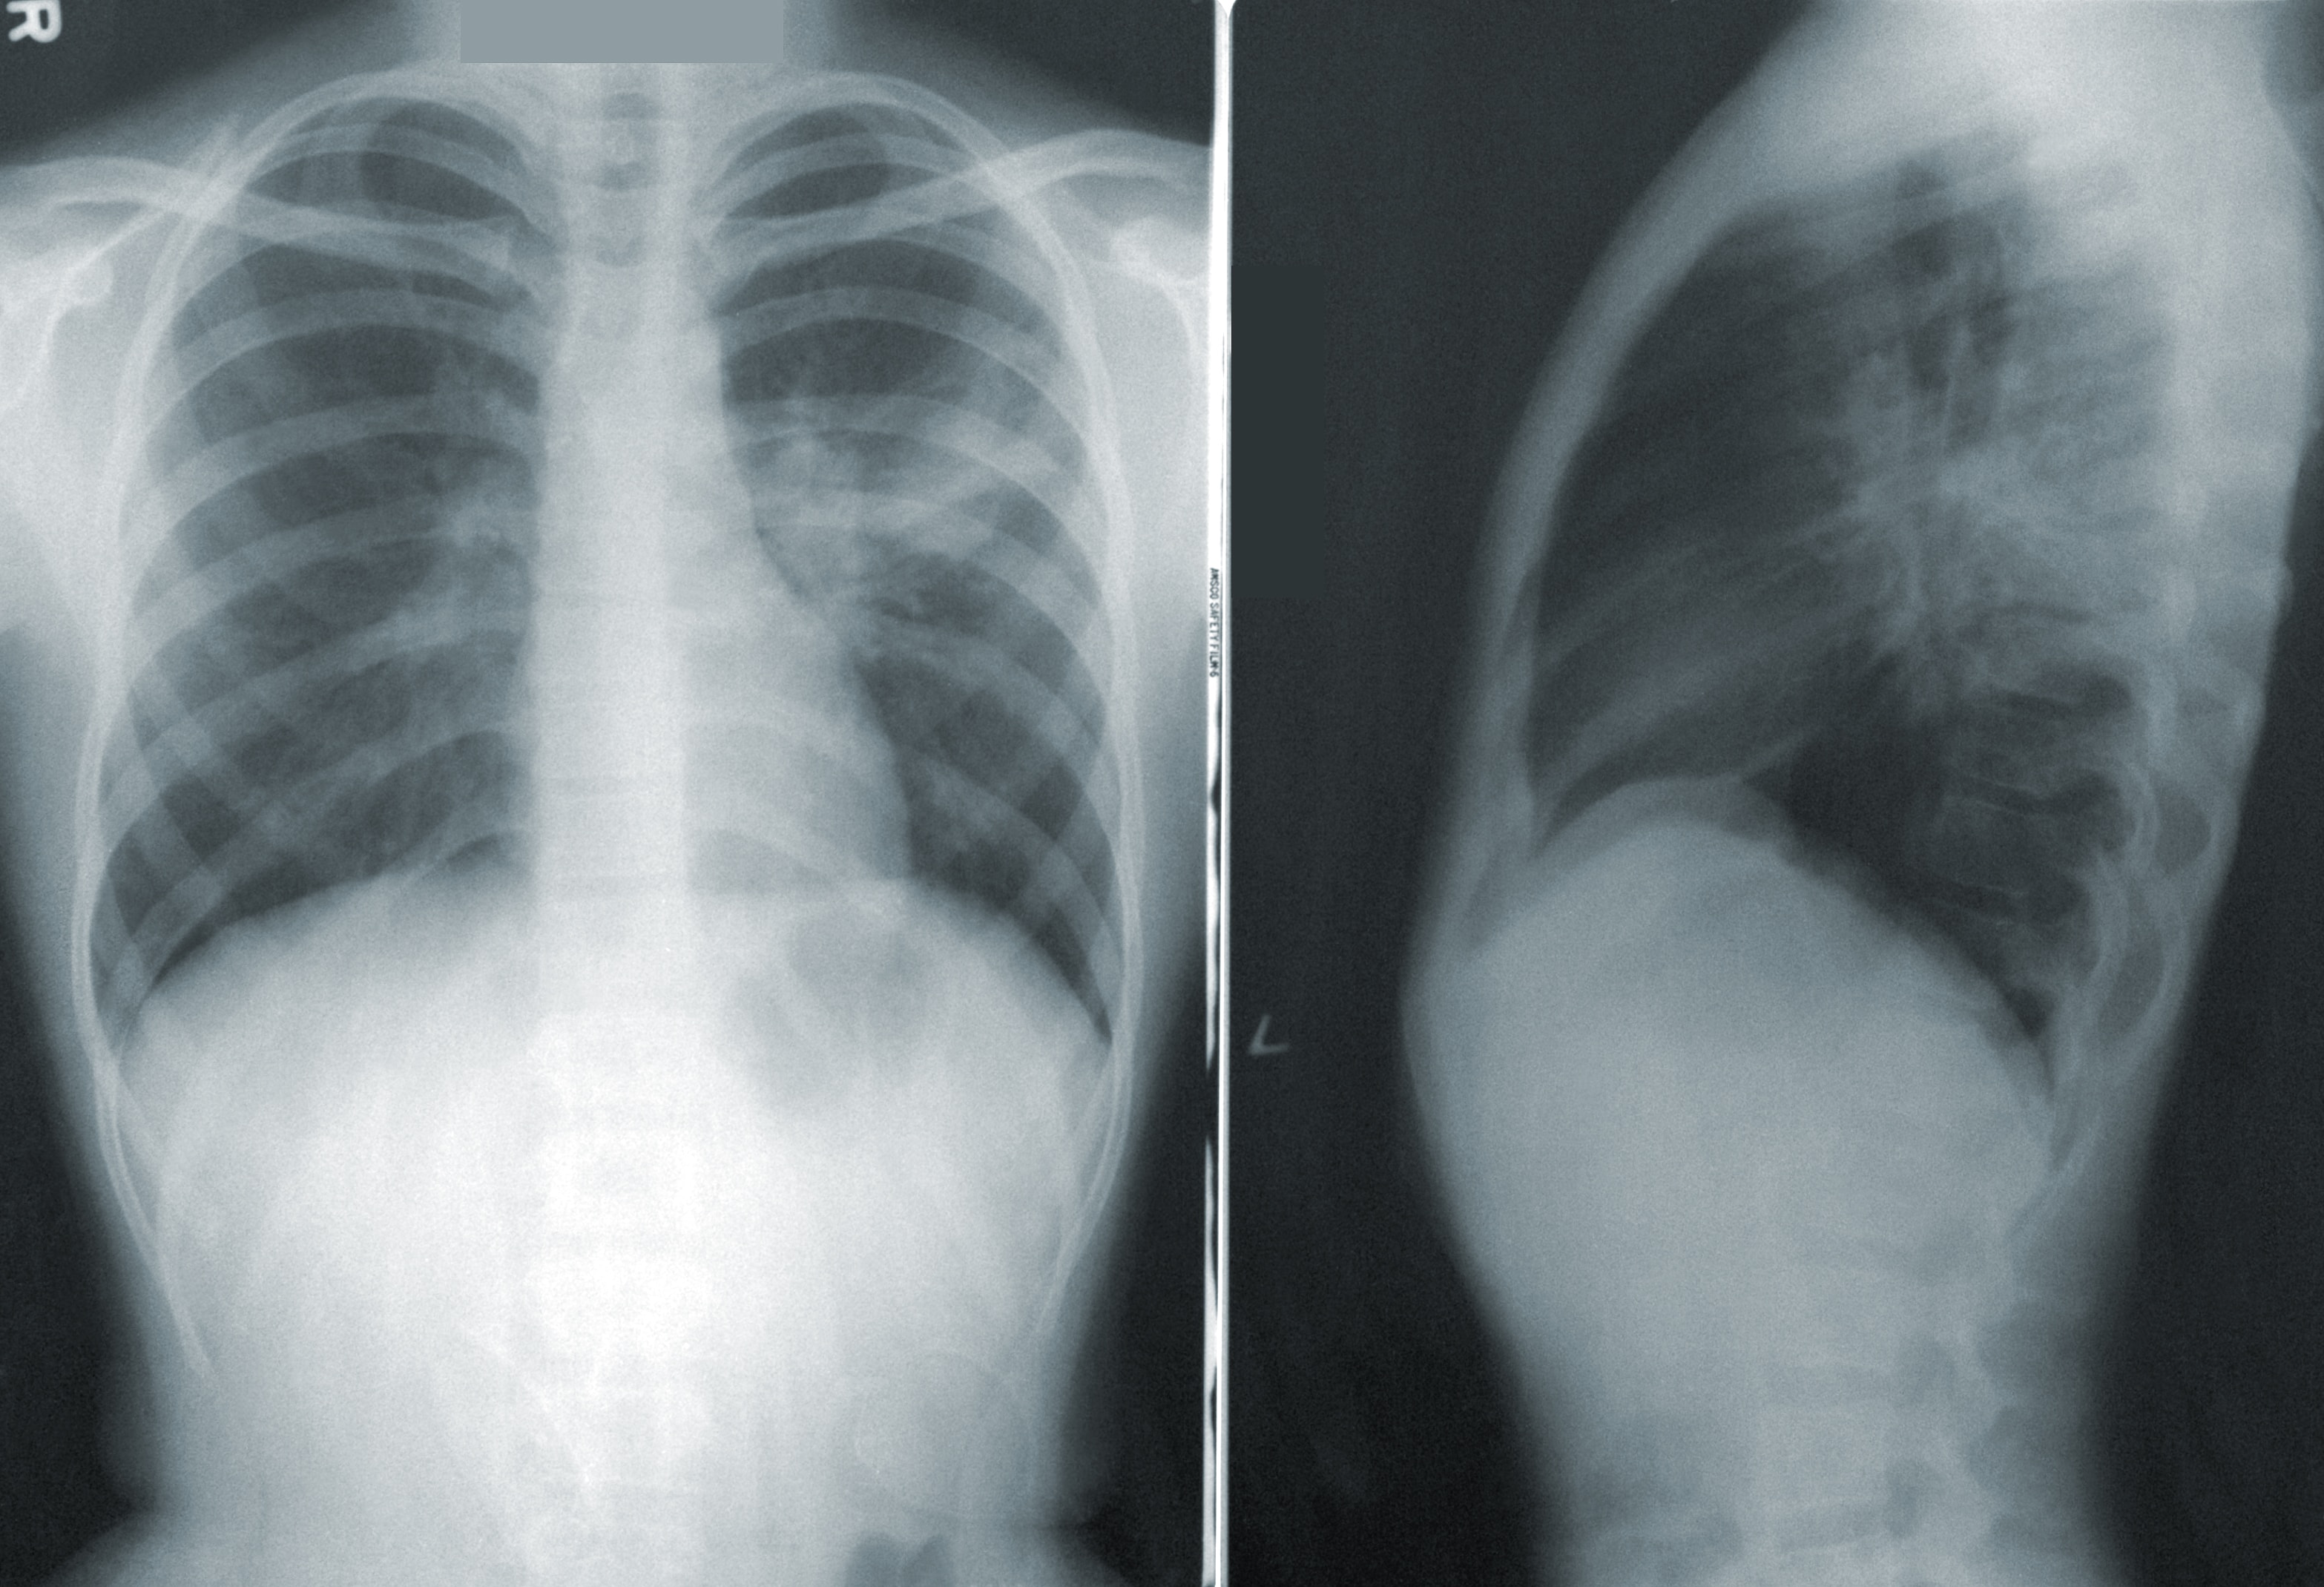

저희 어머니의 폐CT를 봤습니다.

폐유리결절을 처음 봤을 때는 마치 폐에 별이 박힌 듯 한 모습이였습니다.

이 별들이 점점 커지면 폐암이 되는 것이니 마냥 아름다운 별빛은 아닌거지요 ^^

그 중에 2개가 컸기 때문에 폐의 반을 잘라냈습니다.